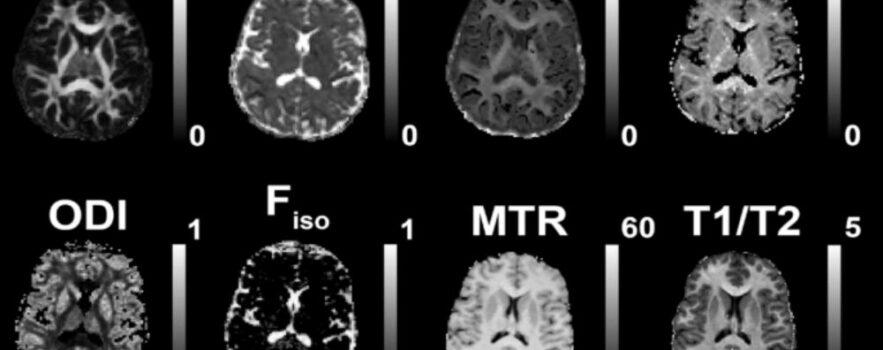

New CamCAN study used 11 different measures to show that white-matter health is multidimensional: 4 latent MRI-derived factors explained 89% of variance, were predicted by vascular health, and predicted cognition